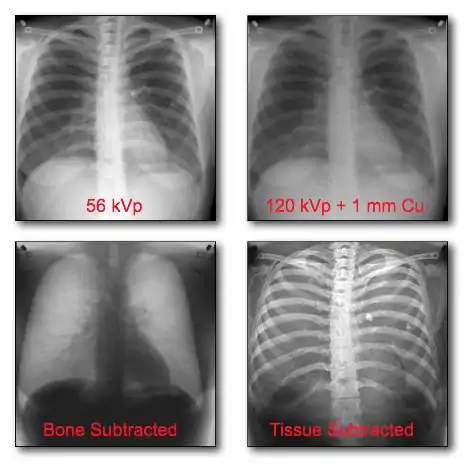

The application of DR technologies has also led the development of new imaging techniques, such as Digital Tomosynthesis and Temporal Subtraction, and to new forms of digital image processing, e.g. rib suppression in chest radiography[14] and Computer-Assisted Diagnosis (CAD)[15]. These topics however are beyond the scope of our considerations here.